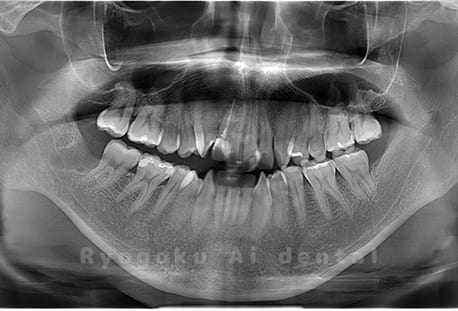

Case03

- 原因

- 上顎、下顎の親知らず

- 治療内容

- 上下4本の親知らずを抜歯したケースです。

<リスク・副作用>

手術後は痛み、腫れ、痺れなどの副作用が生じる場合があります。